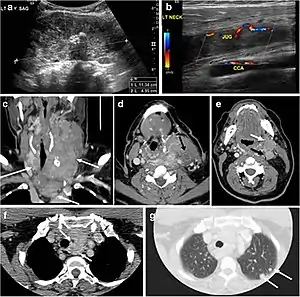

Fig. 13. A 27-year-old female patient known to have goiter. a, b Axial and sagittal enhanced CT scan images of the neck demonstrate a heterogeneously enhancing, enlarged thyroid gland with scattered calcifications (white arrow), cystic changes, and substantial retro-sternal extension (black asterisks). No lymphadenopathy or substantial airway narrowing.[1]

Fig. 14. A 19-year-old male patient known to have multi-nodular goiter and FNA, showing underlying Hashimoto's thyroiditis. a, b Sagittal and transverse greyscale and colour Doppler ultrasound of the neck demonstrate a hypoechoic enlarged right thyroid lobe with small hyperechoic regenerative nodules and marked hypervascularity (white arrows). c, d Enhanced axial CT scan images of the neck demonstrate a heterogeneously enhancing and enlarged thyroid gland, left more than right lobe, and the trachea is markedly narrowed.[1]

Fig. 15. A 33-year-old female patient who presented with neck swelling and pain and was later diagnosed with Hashimoto's thyroiditis. an Axial enhanced CT scan of the neck demonstrates minimal diffuse enlargement of the thyroid gland, especially the isthmus (white arrow). b Transverse greyscale ultrasound of the neck demonstrates heterogeneously enlarged thyroid and thickened isthmus, measuring 8.6 mm.[1]

Malignancy can coexist within the goiter and a CT scan may give a clue if there are abnormal cervical lymph nodes and/or signs of invasion. Retrosternal extension (Fig. 15) could affect the surgical approach, as a lower extent may require a partial or total sternotomy to facilitate complete resection. Therefore, the distance of the retrosternal extent from the sternal notch should be measured on a sagittal image.[1]